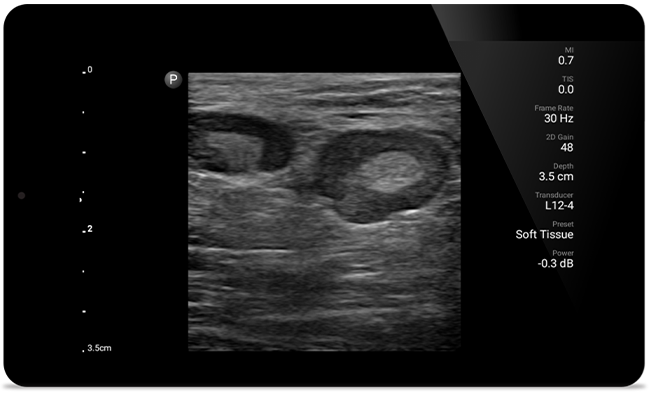

O Lumify ajuda você a ver os detalhes finos em músculos, articulações, ligamentos, tendões e cartilagem para fazer um diagnóstico mais preciso de lesões.

A SonoCT reforça o diagnóstico por imagem real do tecido enquanto elimina artefatos aleatórios. Essa tecnologia produz diagnóstico por imagem superior aos convencionais em até 94% dos pacientes.

• Faixa de frequência de 2 a 5 MHz • Raio de curvatura 50 mm• 2D, Doppler colorido e pulsado*, modo M, XRES avançado e imagem harmônica, SonoCT • Diagnóstico por imagem de alta resolução para aplicações mais profundas: otimizações pré-configuradas para diagnóstico por imagem abdominal, de vesícula, de ginecologia/obstetrícia e de pulmão • Disponivel em Android